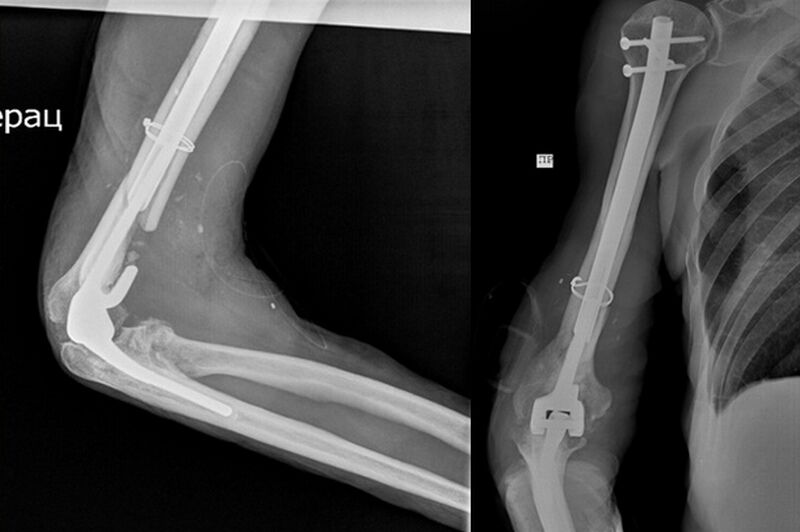

•16.07.24В Кургане врачи Центра Илизарова прооперировали пациента со сложным переломом плеча